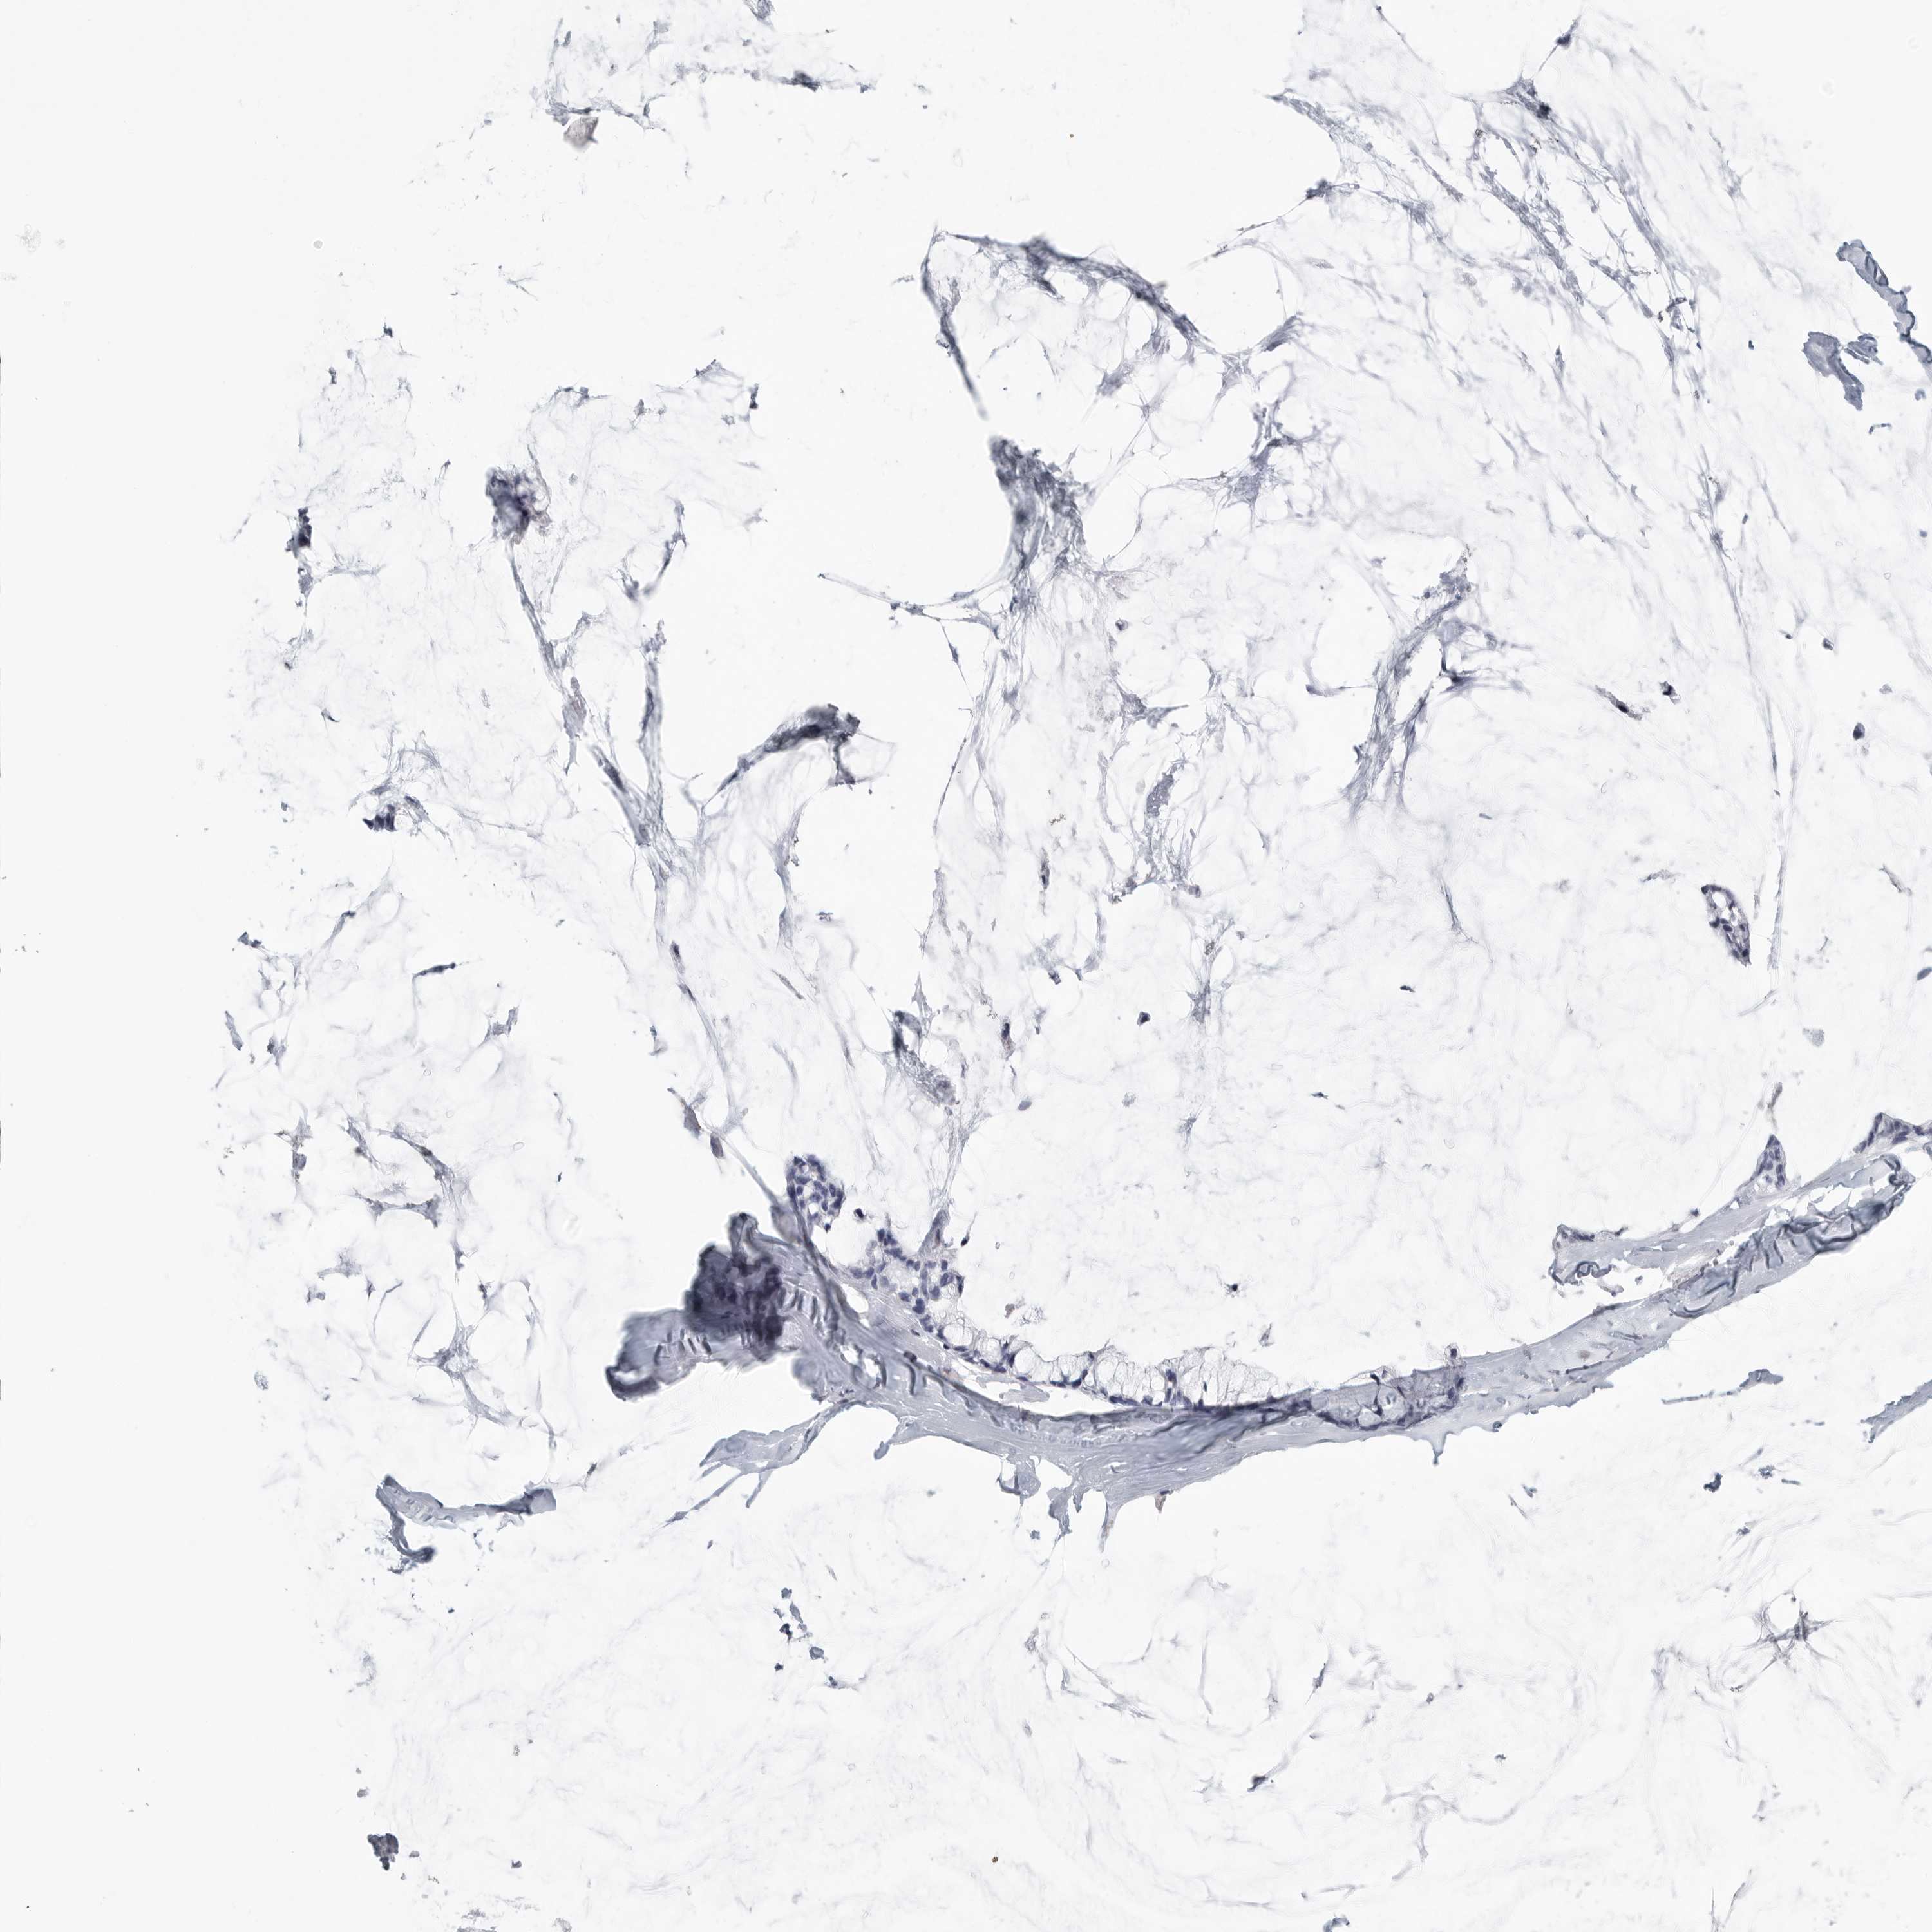

OVARIAN CANCER - Protein expressioni

A mouse-over function shows sample information and annotation data. Click on an image to view it in a full screen mode. Samples can be filtered based on level of antibody staining by selecting one or several of the following categories: high, medium, low and not detected. The assay and annotation is described here.

Note that samples used for immunohistochemistry by the Human Protein Atlas do not correspond to samples in the TCGA dataset.

Antibody stainingi

Antibody staining in the annotated cell types in the current human tissue is reported as not detected, low, medium, or high, based on conventional immunohistochemistry profiling in selected tissues. This score is based on the combination of the staining intensity and fraction of stained cells.

Each image is clickable and will lead to virtual microscopy that enables deeper exploration of all samples and also displays staining intensity scores, fraction scores and subcellular localization as well as patient and tissue information for each sample.

Antibody HPA027134

Antibody HPA027150

Antibody HPA029859

Antibody CAB022343

Staining

High

Medium

Low

Not detected

Intensity

Strong

Moderate

Weak

Negative

Quantity

>75%

75%-25%

<25%

None

Location

Nuclear

Cytoplasmic/membranous

Cytoplasmic/membranous,nuclear

Cystadenocarcinoma, serous, NOS

Carcinoma, endometroid

Cystadenocarcinoma, mucinous, NOS

Carcinoma, NOS